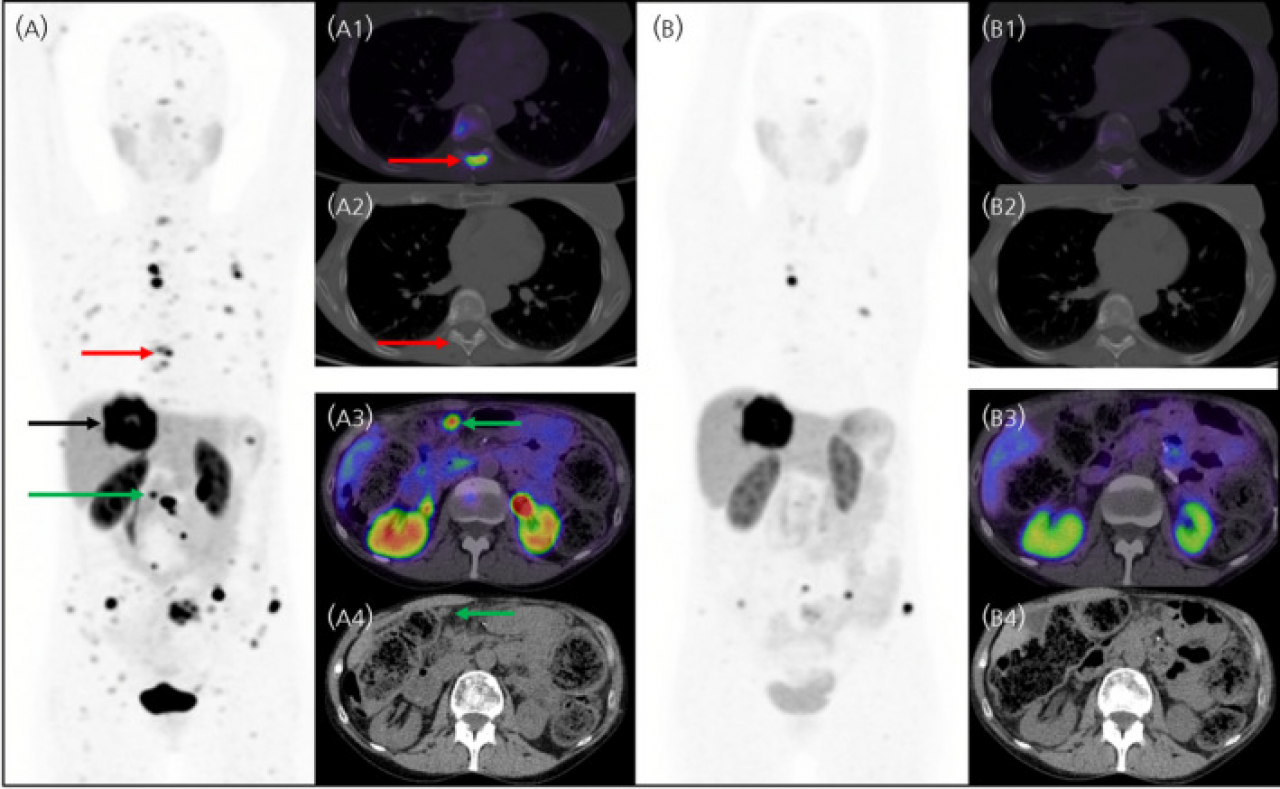

Figure 7: Case demonstrating the role of SSTR PET/CT imaging in diagnosing and evaluating response after PRRT in a 63-year-old woman with metastatic Grade 2 small intestinal NEN. Panel A shows the maximum intensity projection (MIP) image with 68Ga-DOTATATE PET/CT before PRRT, while panel B illustrates the overall reduction of SSTR disease burden after PRRT. Image reproduced from Kong G et al. J Neuroendocrinol. 2025;37(3):e13461. Please refer to the original publication for more detailed information.